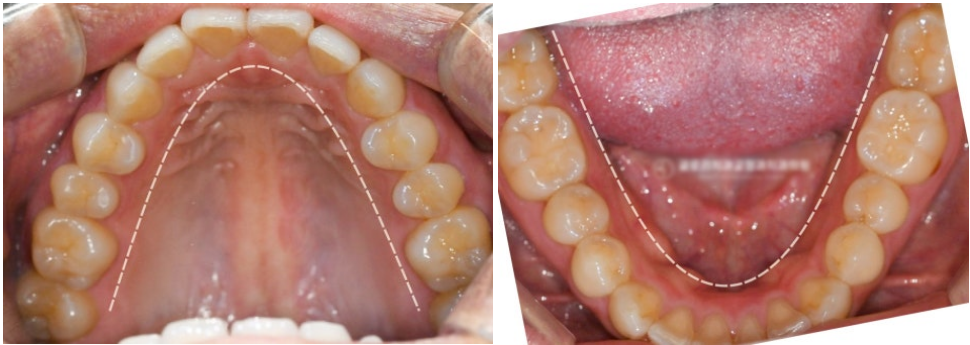

촬영일 :23.06.09

X‑ray상에서는

좌우 아래 끝에 사랑니가 확인되었으며,

촬영일 :23.06.09

골격을 기준으로 아래 앞니 기울기가

과도한 것을 확인할 수 있었습니다.